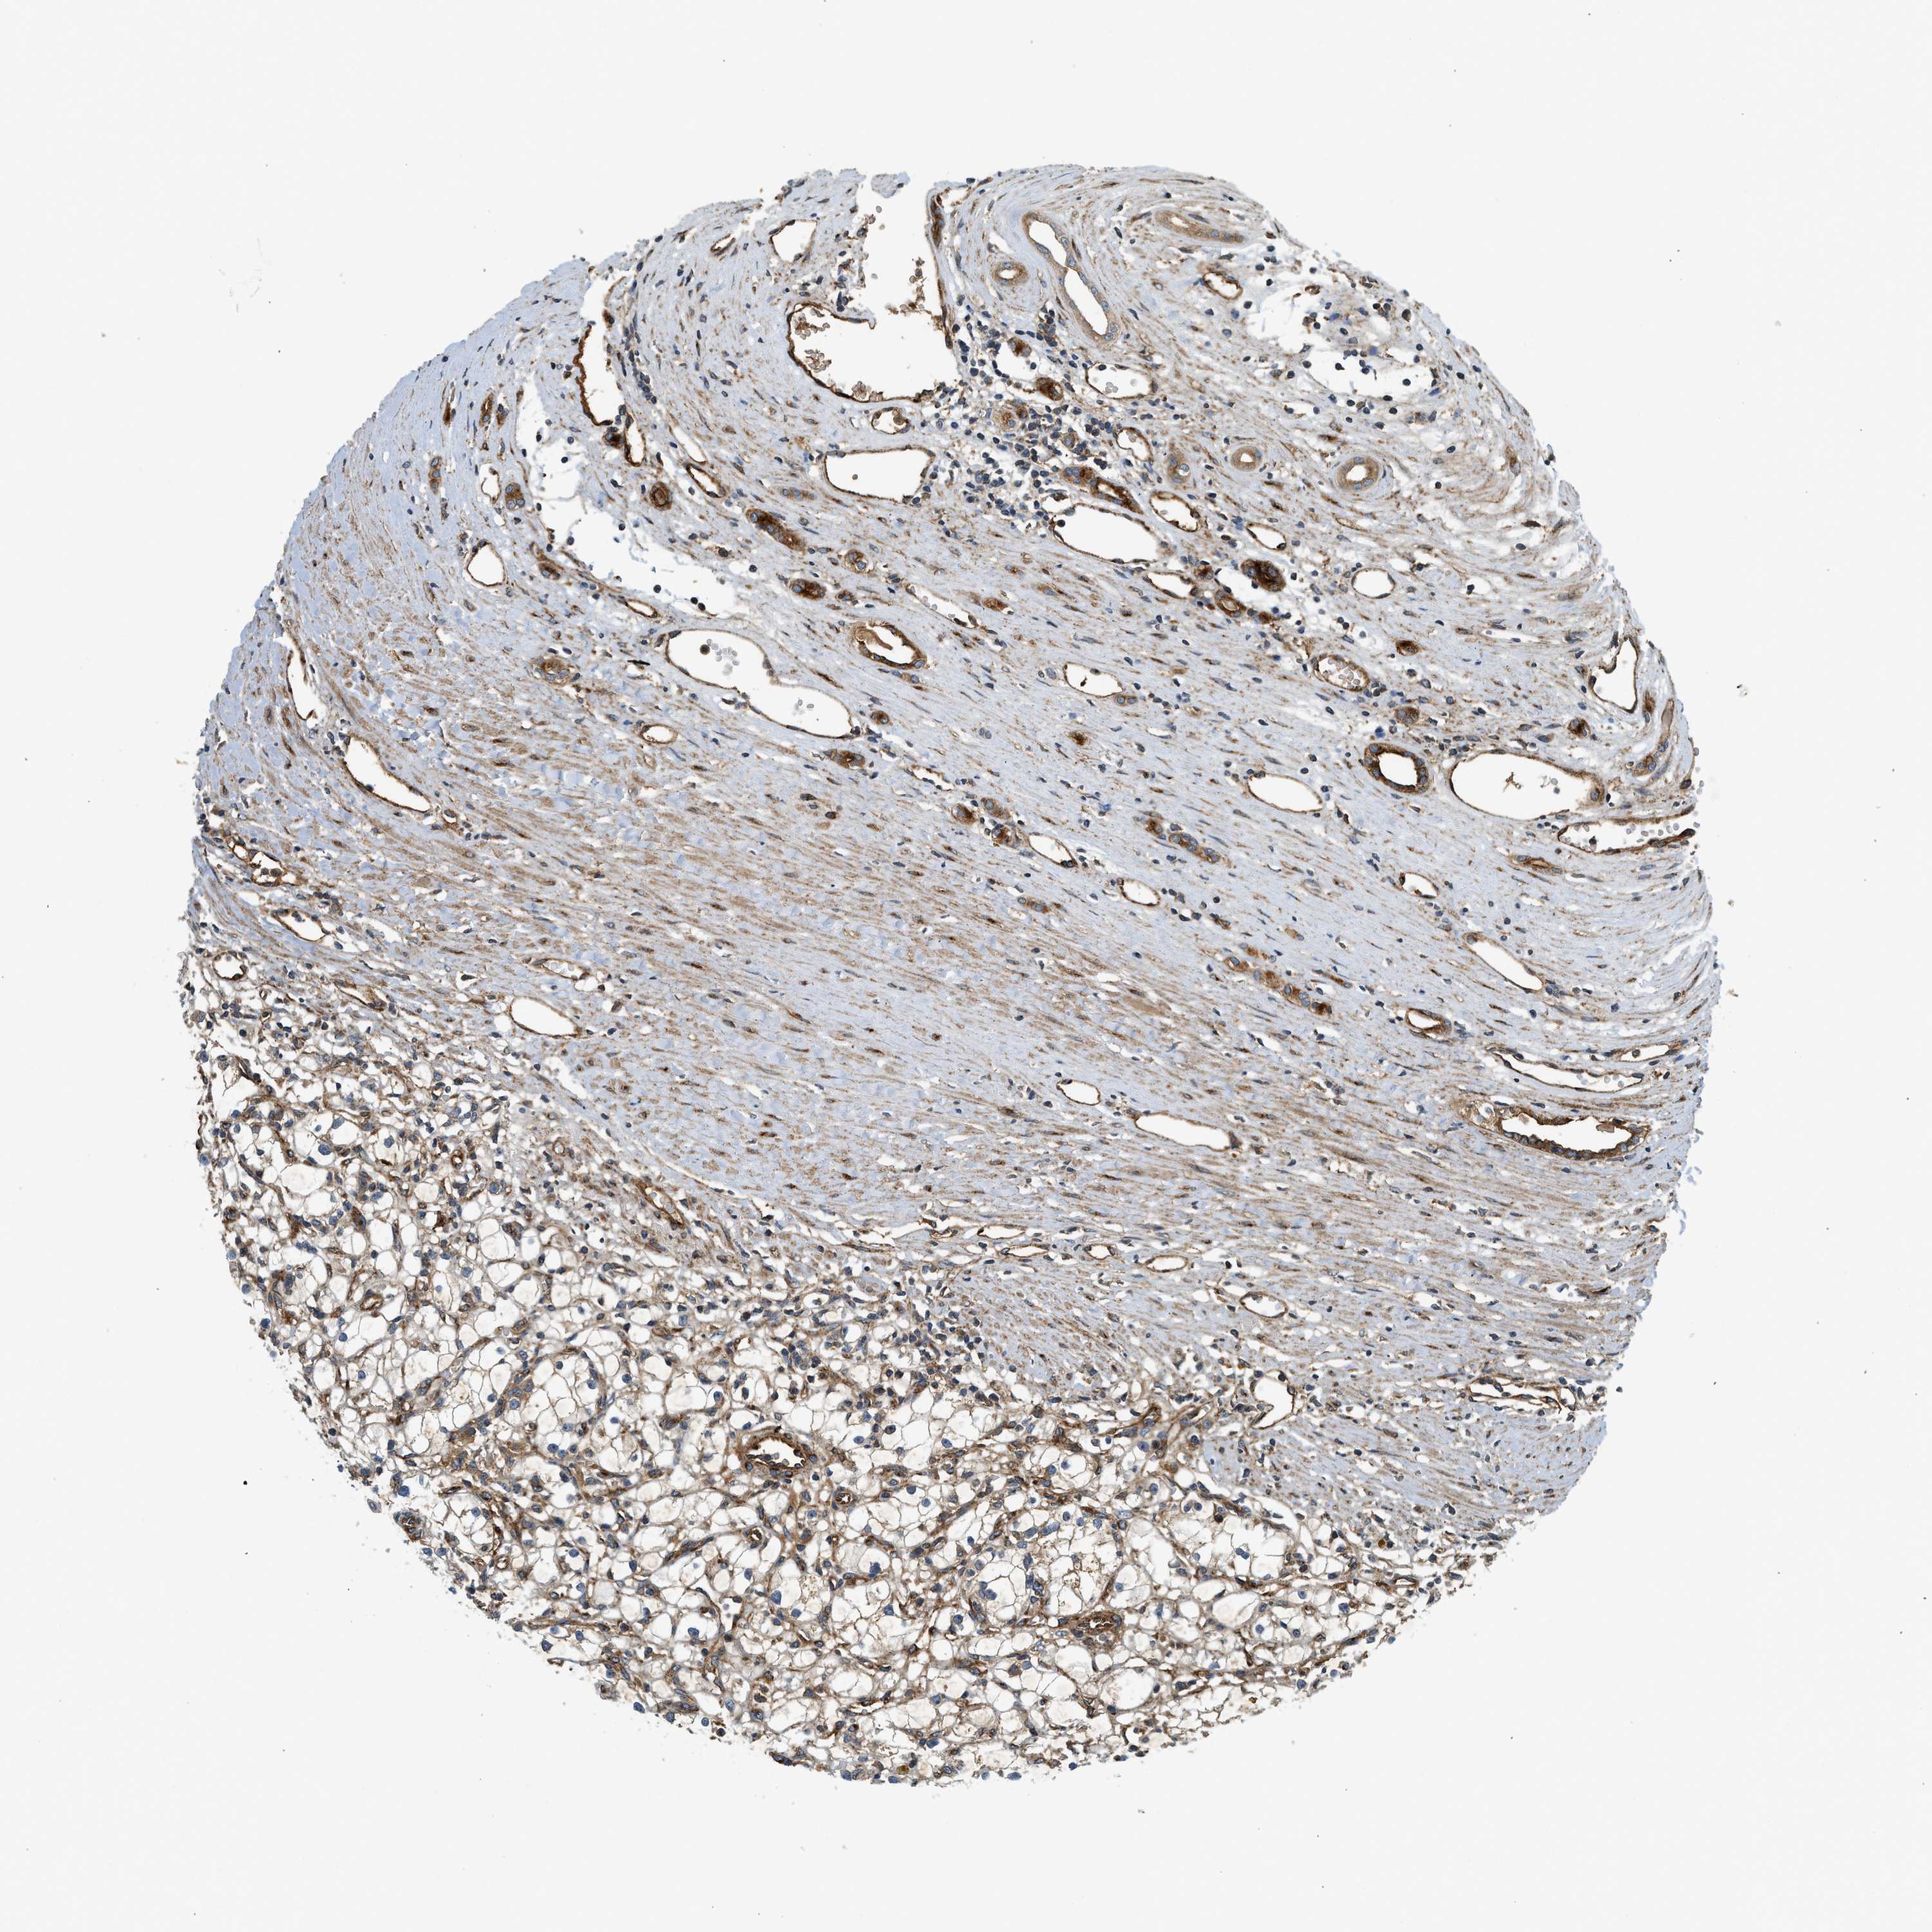

KIDNEY RENAL CLEAR CELL CARCINOMA (VALIDATION) - Interactive survival scatter ploti

The Survival Scatter plot shows the clinical status (i.e. dead or alive) for all individuals in the patient cohort, based on the same data that underlies the corresponding Kaplan-Meier plots. Patients that are alive at last time for follow-up are shown in blue and patients who have died during the study are shown in red.

The x-axis shows the expression levels (FPKM) of the investigated gene in the tumor tissue at the time of diagnosis. The y-axis shows the follow-up time after diagnosis (years). Both axes are complimented with kernel density curves demonstrating the data density over the axes. The top density plot shows the expression levels (FPKM) distribution among dead (red) and alive patients (blue). The right density plot shows the data density of the survived years of dead patients with high and low expression levels respectively, stratified using the cutoff indicated by the vertical dashed line through the Survival Scatter plot. This cutoff is automatically defined based on the FPKM cutoff that minimizes the p-score. The cutoff can be changed by dragging the vertical line or by entering a cutoff value in the square labeled "Current cut-off".

Under the Survival Scatter plot the p-score landscape (black curve; left axis) is shown together with dead median separation (red curve; right axis). Dead median separation is the difference in median mRNA expression between patients who have died with high and low expression, respectively. It is calculated as follows: median FPKM expression of dead patients with high expression - median FPKM expression of dead patients with low expression. This is intended to aid the user in visually exploring custom cutoffs and the associated p-scores and dead median separation.

Individual patient data is displayed and can be filtered by clicking on one or more of the category buttons on the top of the page. Categories describing expression level and patient information include: high, low, alive, dead, female, male and tumor stages. The scale of the x-axis can be toggled between linear and log-scale by clicking on the "x log" button. Mouse-over function shows TCGA ID, patient information and mRNA expression (FPKM) for each patient.

& Survival analysisi

Kaplan-Meier plots summarize results from analysis of correlation between mRNA expression level and patient survival. Patients were divided based on level of expression into one of the two groups "low" (under cut off) or "high" (over cut off). X-axis shows time for survival (years) and y-axis shows the probability of survival, where 1.0 corresponds to 100 percent.

HIP1 is validated prognostic, high expression is favorable in Kidney Renal Clear Cell Carcinoma (validation)

Best expression cut offi

Based on the FPKM value of each gene, patients were classified into two groups and association between prognosis (survival) and gene expression (FPKM) was examined. The best expression cut-off refers the FPKM value that yields maximal difference with regard to survival between the two groups at the lowest log-rank P-value. Best expression cut-off was selected based on survival analysis .

When clicking on this number, the vertical dashed line indicating cut-off, the interactive survival plot, and the Kaplan-Meier curve will be adjusted to show results based on the best expression cut-off.

: 19.11

TCGA RNA samplesi

RNA-seq data is reported as average FPKM (number Fragments Per Kilobase of exon per Million reads), generated by the The Cancer Genome Atlas (TCGA) .

Normal distribution across the dataset is visualized with box plots, shown as median and 25th and 75th percentiles. Points are displayed as outliers if they are above or below 1.5 times the interquartile range. FPKM values of the individual samples are presented next to the box plot.

Average pTPM 17.6

Number of samples 100